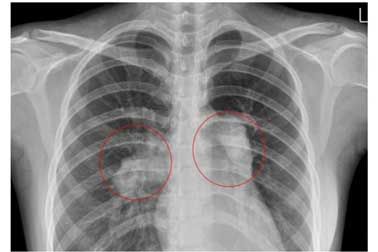

심전도의 우심실 비대 소견

양측 근위부 폐동맥 확장

(4) 심전도검사, 흉부단순촬영, 혈액검사, 흉부CT촬영,운동부하검사,심초음파검사,심도자검사 등을 시행합니다.

우심실 확장과 증가된 우심실 압력으로 심실중격이 좌심실로 밀리는 초음파 소견